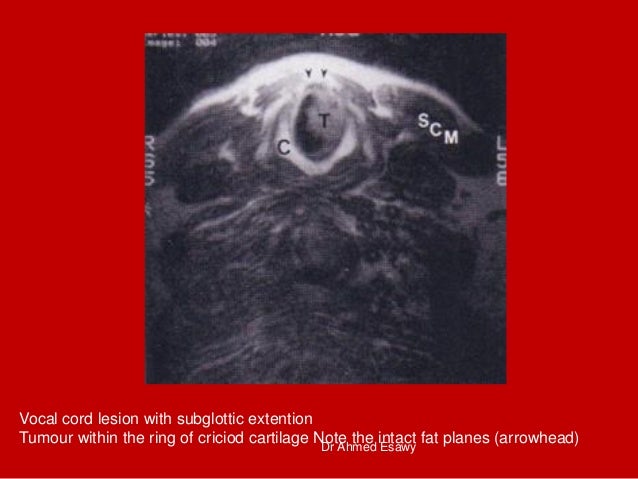

45. 45. Vocal cord lesion with subglottic extention Tumour within the ring of criciod cartilage Note the intact fat planes (arrowhead) Dr Ahmed Esawy